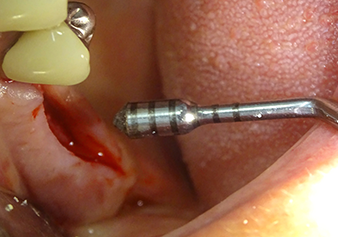

Затем, с помощью инструмента I2A (диаметр 2,0 мм), дно пазухи перфорировалось периодически и в минимально возможном диапазоне. Этот специфический пьезохирургический метод гарантирует, что мембрана Шнейдера не будет повреждена. При использовании Z25P, мембрана уже была слегка приподнята охлаждающей жидкостью, подаваемой через наконечник инструмента (рис. 3). Во избежание высокого давления в ложе имплантата, количество охлаждающей жидкости составляло не более 50%.